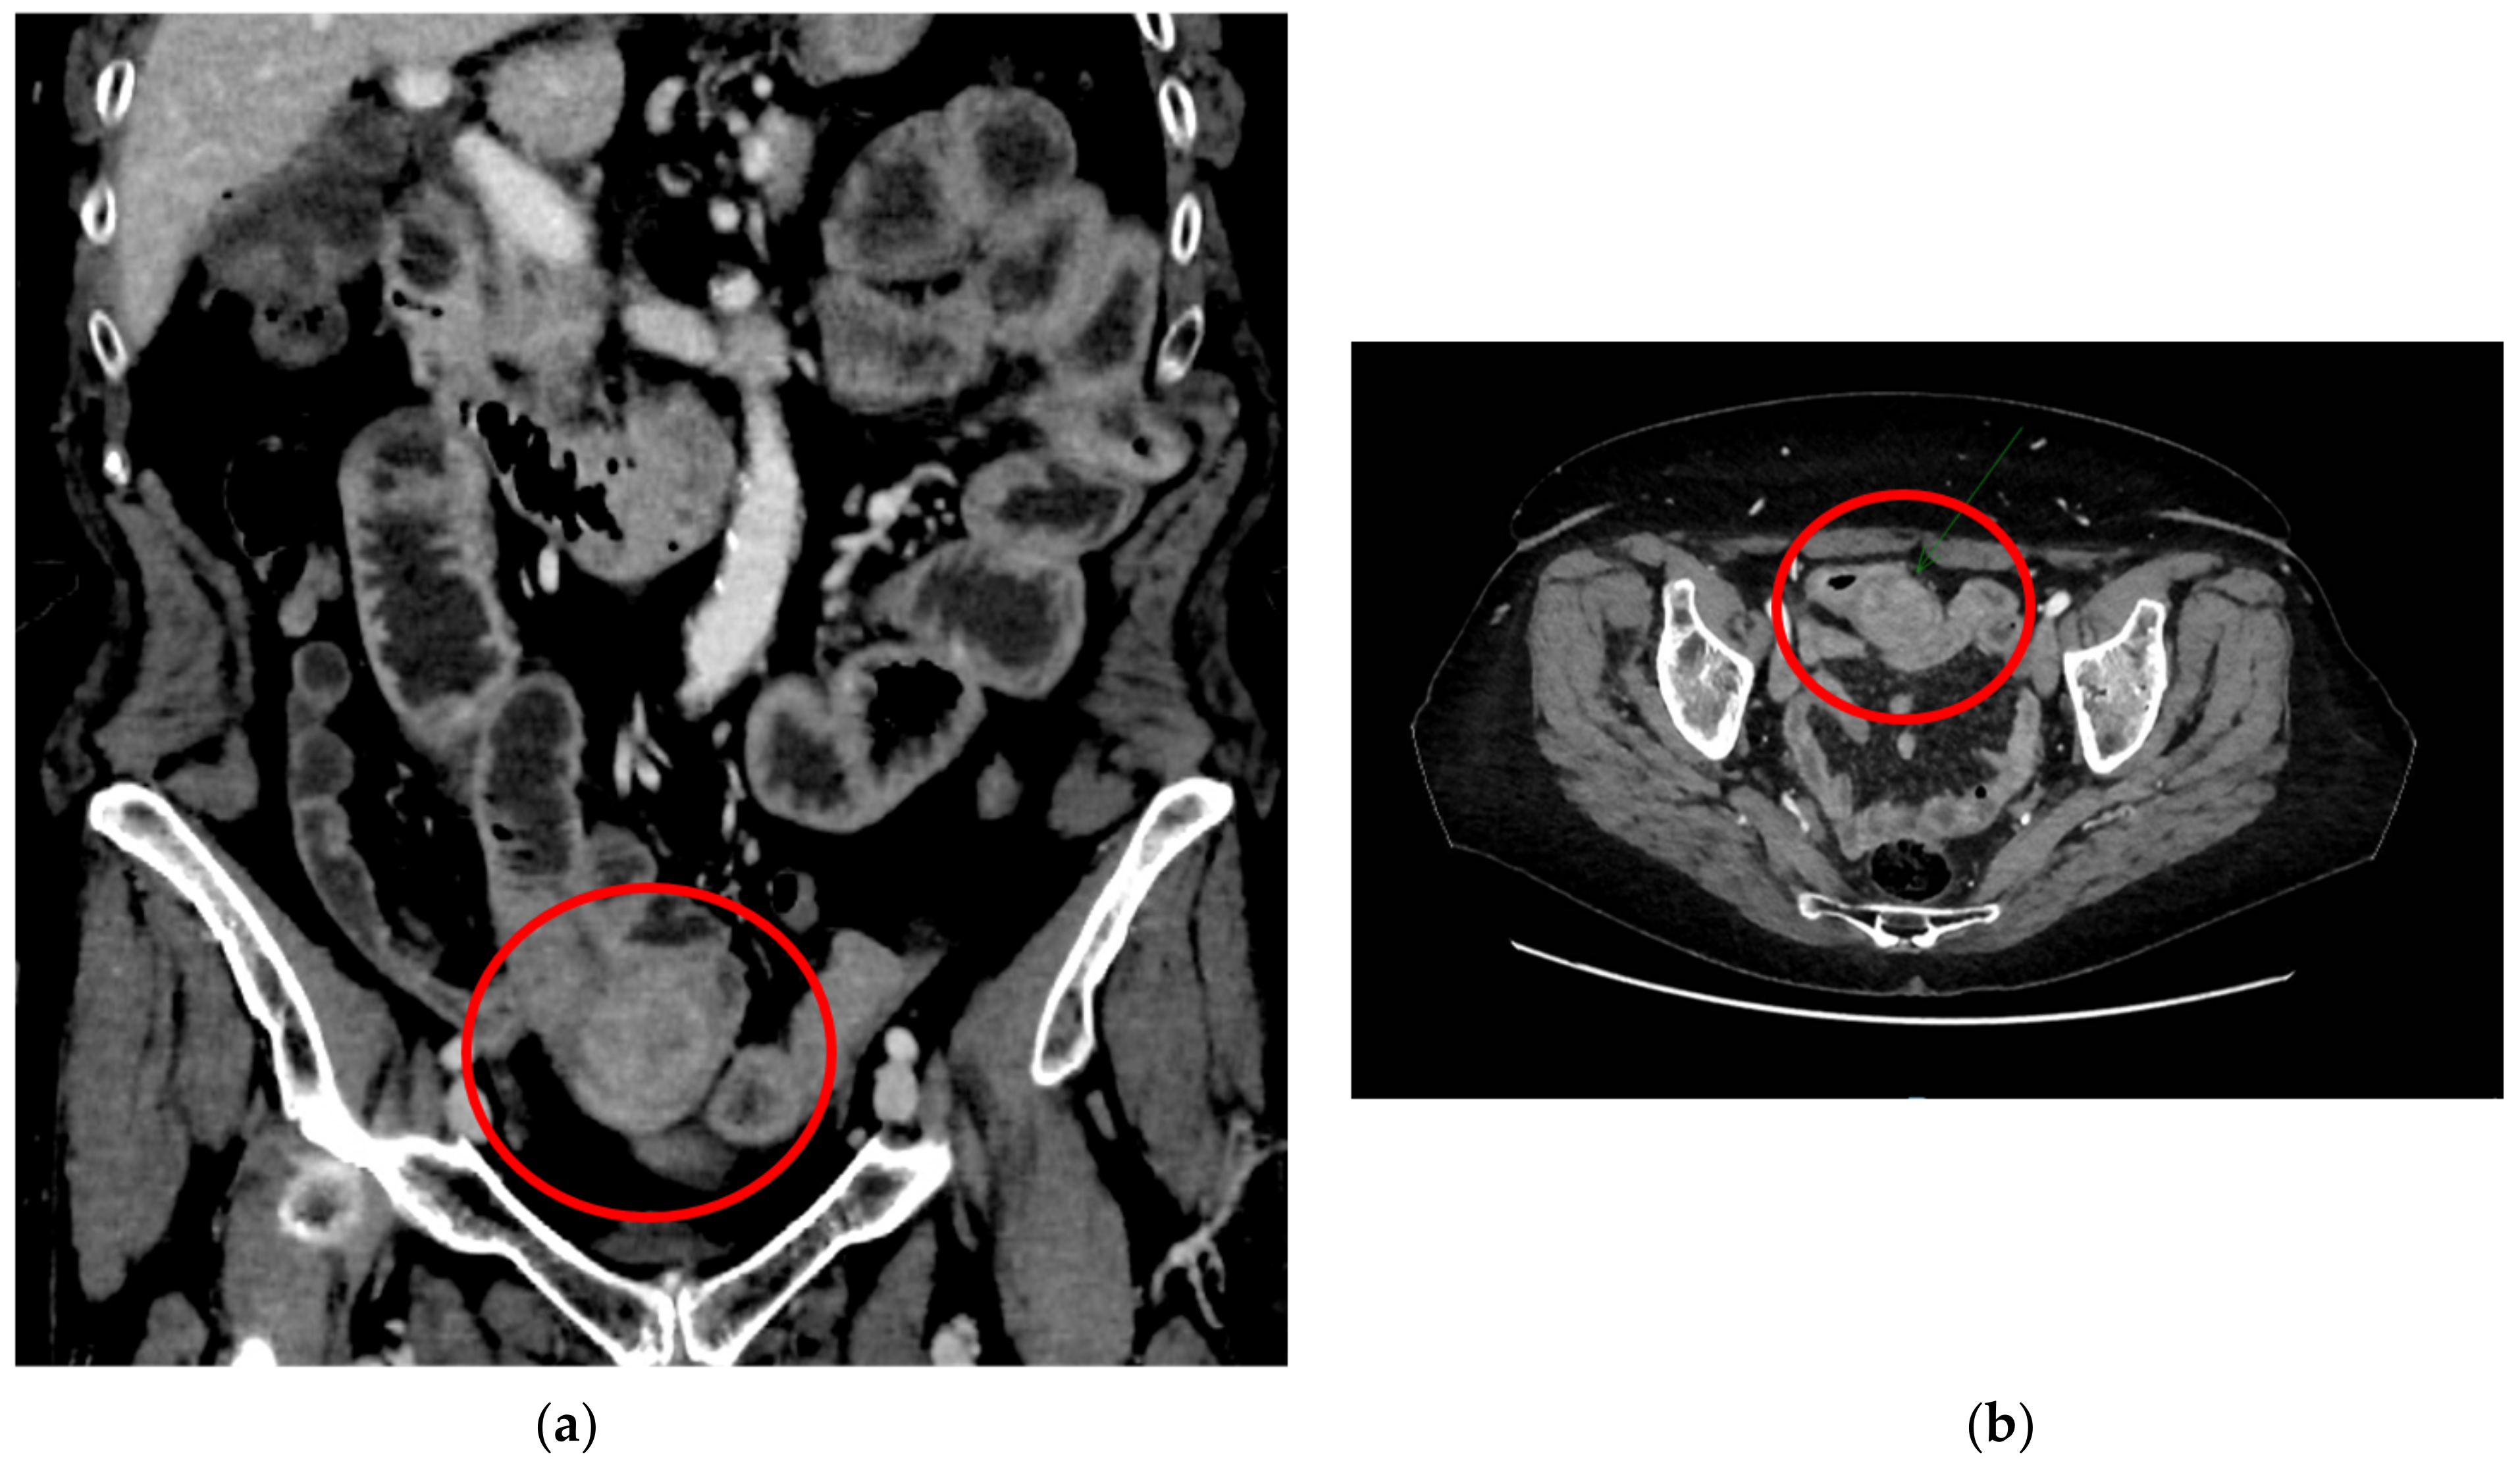

A CT abdominal scan was performed in the suspect of intestinal obstruction showing a mass of about 30 mm involving the small bowel, complicated by an ileal–ileal invagination, and a right ovarian lesion of about 40 mm suspected as hamartoma (Figure 1a,b). The patient was, therefore, hospitalized in our surgical department and, considering the global good conditions, was initially treated with conservative therapy.

Figure 1.

The circles show the mass involving the small bowel and the ileal–ileal invagination in the delayed phase: (a) sagittal plane; (b) transversal plane.